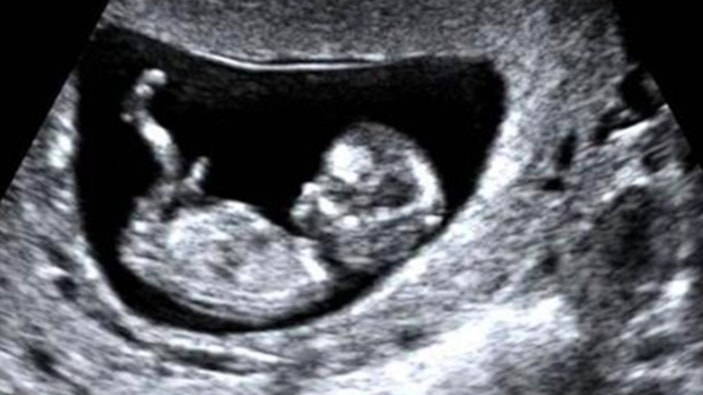

Cinsiyet değiştirme süreci işleyen Marco isimli kişinin, rahmini aldırma işlemi öncesinde 5 aylık hamile olduğu öğrenildi. Bebeği doğurmaya hazırlanan Marco, biyolojik anne olsa da doğum sonrası baba olarak kaydedilecek.

Ülkede erkek olmak için mastektomi ameliyatı geçiren transın, 5 aylık hamile olduğu öğrenildi.

Marco'nun bugüne kadar geçirdiği işlemlerden fetüsün etkilenip etkilenmediği konusunda endişeler de arttı.